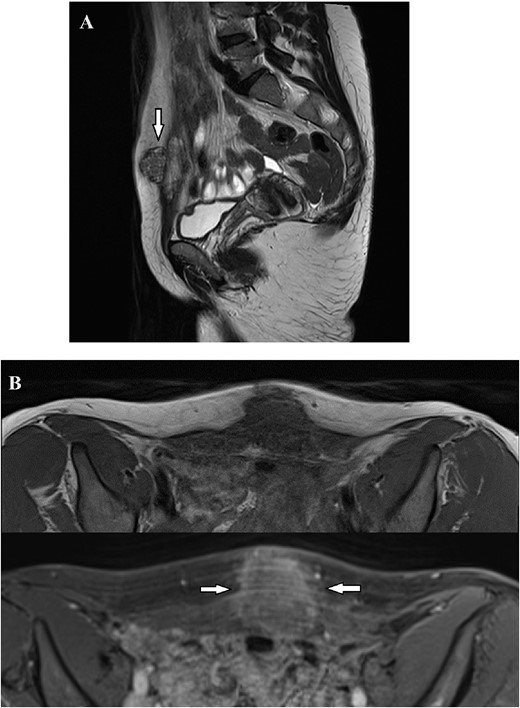

In March, 2022, a 46 year-old woman underwent a laparoscopic supracervical hysterectomy for leiomyomas. Her obstetric history included a cesarean birth 10 years ago. The remaining history was unremarkable. Intraoperatively, no sign of endometriosis was found. Supracervical hysterotomy was carried-out with a monopolar knife. Following placement in a sealed bag, the morcellated uterine corpus was exteriorized through the right iliac port. Pathologic examination confirmed common leiomyomas. In April, 2023, the woman presented to her GP complaining of a cyclically painful suprapubic lump. An ultrasonography scan showed a 4 cm inhomogeneous mass with mild vascularization, extended from the rectus muscle to subcutaneous fat. Magnetic resonance imaging (MRI) confirmed a solid irregularly-shaped mass with high contrast enhancement signal (Fig. 1). To rule-out a malignancy the patient underwent oncologic consultation and a through-cut needle biopsy was performed, yielding a diagnosis of endometriosis. The patient came to gynecological consultation in September, 2023. A hard mass, fixed to the underlying abdominal wall layers just beneath the scar of suprapubic trocar insertion was found at physical examination. We planned continuous oral administration of a Progestogen (Dienogest, 2 mg/day). Within the next two months the patient experienced pain symptoms relief but a mass remaining stable in size was found. In February, 2024, the patient underwent laparotomic excision (Fig. 2). Surgical assessment showed an endometriotic infiltration from subcutaneous tissue to fascia transversalis, sparing the peritoneum. The resection was conducted obtaining at least 5 mm margin-free tissue and later, a fascial mobilization from rectus muscles led to a tension-free primary closure (Fig. 3). Progestogen therapy was continued for six months after surgery. The histopathology confirmed an endometriotic tissue with coexistent smooth muscle-cells proliferation, staining positively to Desmin and negatively to Myogenin immunohistochemistry, leading to the diagnosis of extrauterine adenomyoma (Fig. 4). Six months after surgery, no relapsing disease nor incisional hernia were found.

Magnetic Resonance Imaging showed a solid irregularly shaped mass with high contrast enhancement signal, measuring 36×32×26 mm infiltrating the abdominal wall. (A) Nodular formation (arrow) infiltrating the suprapubic area, exhibiting heterogeneous signal in T2-weighted images, extending from the subcutaneous tissue to the transversalis fascia. (B) T1 Weighted images before and after intravenous contrast of Dotarem. Following the contrast infusion, heterogeneous post-contrast enhancement was observed (arrows).